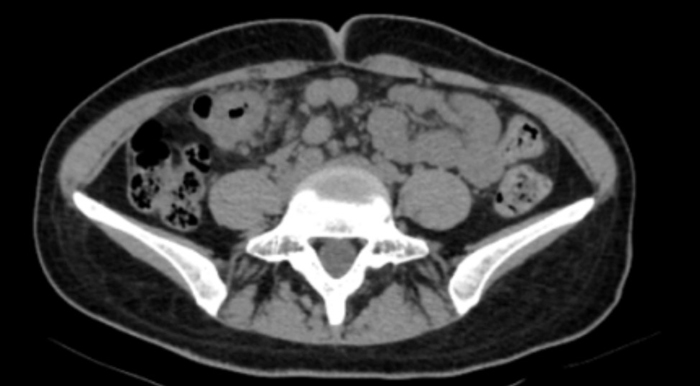

“脐周疼痛对应的多是小肠问题,右上腹的包块却指向肝胆、结肠等器官,这两者对不上。”医生立刻警觉起来,当即安排王女士做腹部CT检查。影像结果很快出来:结肠近肝曲处肠壁可疑增厚,肠腔狭窄——这个信号让诊疗团队的神经瞬间紧绷。

三天后,消化内镜中心孙舒仰医生操作的结肠镜顺利进行。当镜头探至升结肠近肝曲——正是之前查体摸到包块的位置时,一个不规则肿物赫然出现:它环绕肠腔2/3,表面糜烂溃疡还附着污苔,质地脆弱一碰就出血,肠壁已变得僵硬,管腔也出现偏心性狭窄,万幸肠镜还能勉强通过。“高度怀疑结肠癌。”孙舒仰医生当场判断。

几天后的病理报告印证了这一结论:中分化腺癌。“原来腹痛、大便不成型是肠腔狭窄导致的不完全性肠梗阻,进食后压力增大就疼,排便后缓解。”医生解释道。从首次就诊到病理确诊,全程仅用6天,这背后是消化内科、影像科、内镜中心、病理科的高效协同作战。目前,王女士已转至肿瘤科和普外科接受进一步治疗。